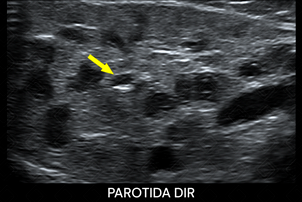

Descrição das figuras: Pré-escolar, 4 anos, com relato materno de abaulamento na face direita e febre. Mãe refere outros episódios prévios. Realizada ultrassonografia cervical que evidenciou aumento da glândula parótida direita, com textura heterogênea e áreas hipoecoicas, com focos hiperecogênicos puntiformes no seu interior (setas amarelas). Correlacionando história clínica e achados de imagem, devemos pensar em parotidite recorrente da infância. [cms-watermark]

• O exame de imagem de escolha , por se tratar de paciente pediátrico, é a ultrassonografia cervical por que favorece a boa avaliação das glândulas salivares, inclusive da parótida. Nela observaremos a glândula com dimensões aumentadas, heterogênea, com áreas hipoecoicas de permeio, contendo focos ecogênicos puntiformes no seu interior, correspondendo aos ductos ectasiados. Observam-se, ainda, linfonodos intra-parotídeos (figuras acima) ;